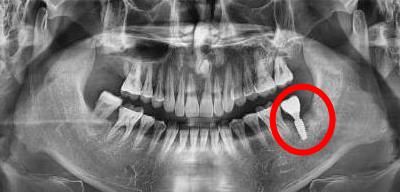

後牙種植牙後拍片

2、種植牙術前以及術後複診都會(hui) 涉及到拍X光片,或者是CT片分析牙齒缺失和種牙後使用情況,而拍攝X光等檢查可能會(hui) 造成流產(chan) 等不良影響。